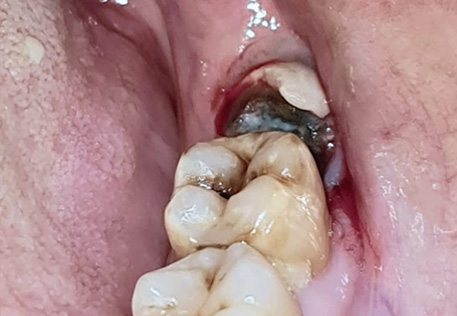

Before / After